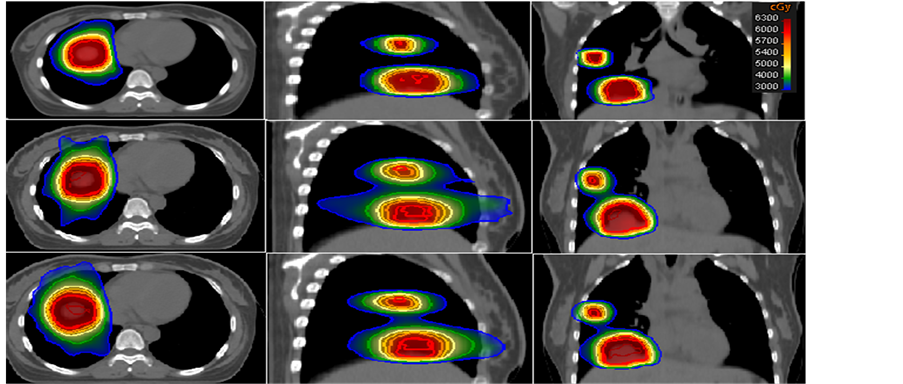

Figure 1. Isodose of one patient on Tomotherapy (top), Non-coplanar (middle), and Coplanar (bottom) in axial, sagittal and coronal planes.

RTOG0236 asked to report the R50% values, the ranges of ratios of 50% prescription isodose volume to PTV for Tomotherapy, Pinnacle coplanar and non-coplanar were from 2.32 to 9.11 Gy, 7.45 to 14.03 Gy, and 6.98 to 10.71 Gy, respectively. A statistical significance was observed compare Tomotherapy to non-coplanar (p = 0.004) and coplanar (p < 0.0001) (Figure 1).